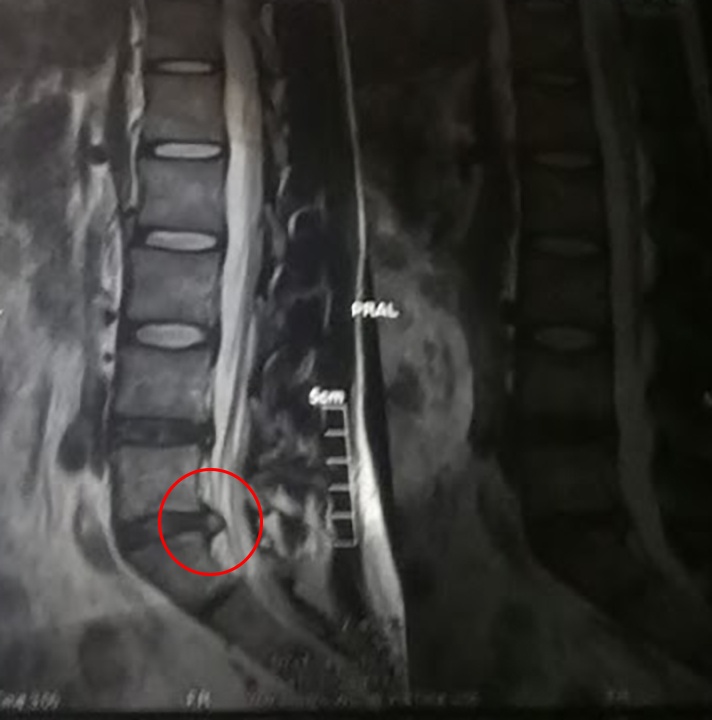

МРТ показало довольно печальную картину — остеохондроз, одна протрузия и одна грыжа в поясничном отделе — собственно, она, родная, изображена на фото внизу. Консультация нейрохирурга была довольно быстрой и четкой — “операция, вам, молодой человек не показана, живите так, делайте зарядку и всего вам хорошего!”. Я помню мысли тогда у меня были от мрачных до самых мрачных типа “ну, самое страшное — это грыжа перетрет мне нерв, я не буду чувствовать ногу, мне ее ампутируют, это же еще не конец света, можно ведь жить и с одной ногой...”. Читатель в состоянии сам представить себе состояние человека, который считал себя более или менее здоровым и вдруг узнает о необратимых или малооборотных изменения внутри его тела.